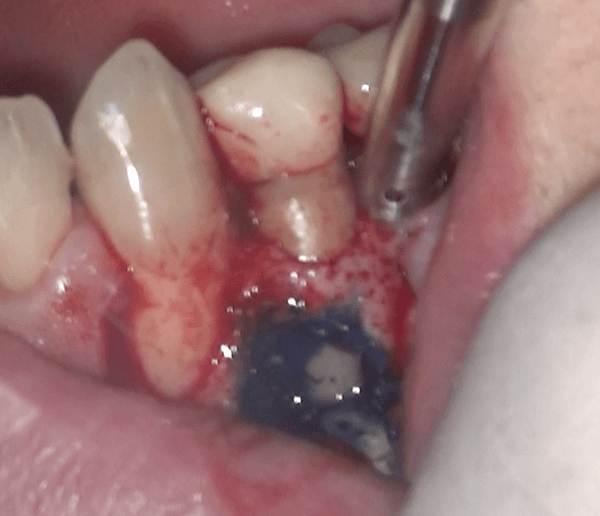

歯茎が腫れている左下の小臼歯

左下の歯茎が腫れているとのことで来院されました。

診査の結果、根管治療が必要と判断し、治療を始めました。

歯茎を切開し、根の状況を確認しました

歯茎を切開し、